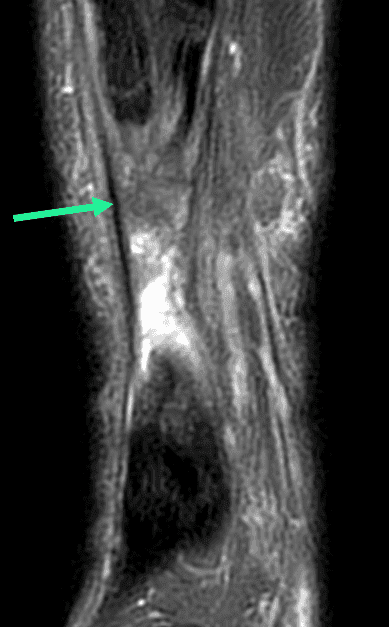

Rupture complète du tendon calcanéen

Douleur aiguë de l'arrière-pied chez un patient de 70 ans lors d'un changement de direction brutale pendant la marche.